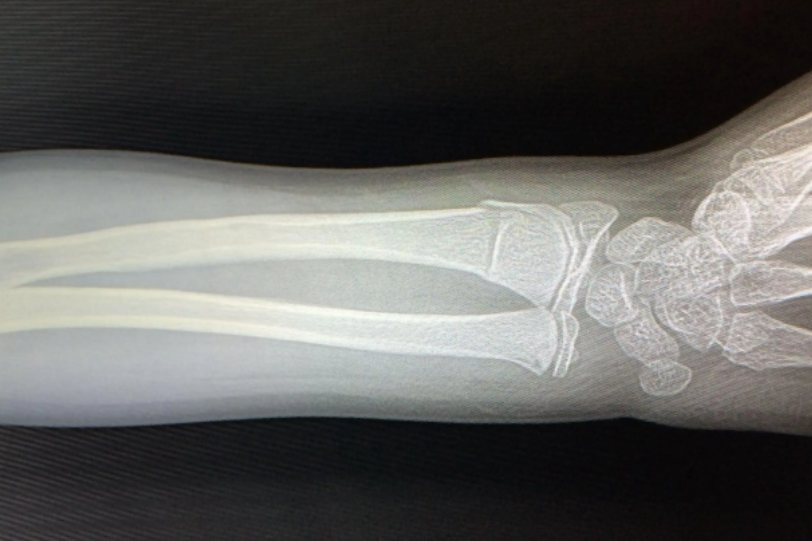

青枝骨折,顾名思义就是像青枝一样柔软的长骨发生骨折,形容一种折而不断的状态,属于稳定性骨折。

青枝骨折通常发生于儿童,儿童的骨骼有机质含量多且骨外膜厚,因此儿童长骨柔软有弹性,不容易发生骨折。

患者在出现青枝骨折时主要表现为患处局限性的肿胀、疼痛,并且伴有瘀斑。发生青枝骨折的骨骼一般不会出现明显的断裂和移位,因此有时候难以触摸到骨折断端。青枝骨折的骨折部位更多是表现为弯曲畸形。虽然患肢功能和活动受限,但是仍然可以保持一定的活动范围,因此也容易被家长忽视。